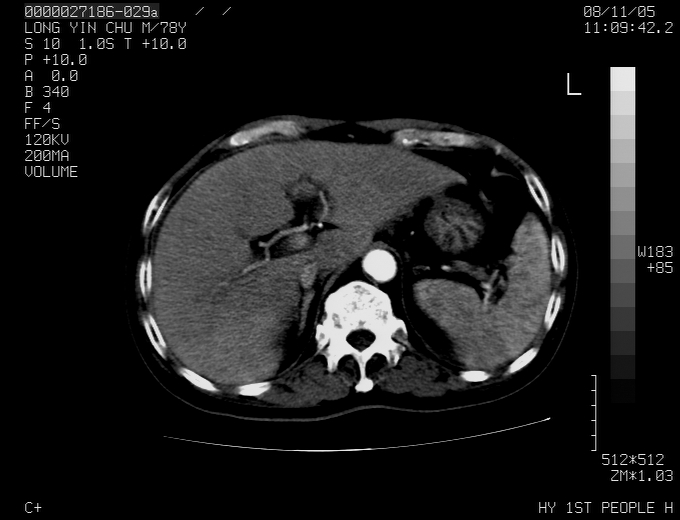

标题: CT16532:M78Y,肝脏病变,请会诊 [打印本页]

标题: CT16532:M78Y,肝脏病变,请会诊

腹胀,腹痛就诊,男性,78岁,外院b超未见异常。

肝ca,脾肾转移

支持脾肾转移瘤,双侧胸腔积液。

考虑弥漫性肝癌并脾及双肾转移.双侧胸水.

图片质量欠佳:多考虑:左侧肾癌。脾脏转移!胸膜转移!

肝脾肾转移瘤可能性大,左肾不除外梗塞,双侧胸水

考虑弥漫性肝癌并脾及双肾转移,双侧胸水。

考虑肝癌并双肾及脾脏转移;双侧胸腔积液。